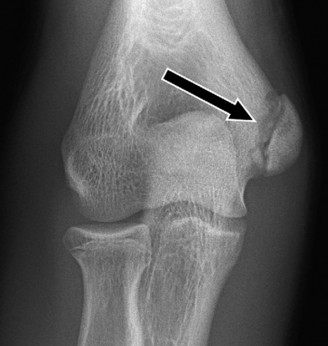

A 9-year-old, baseball pitcher presents to the office with 4 weeks of elbow pain of his throwing arm. He deni…